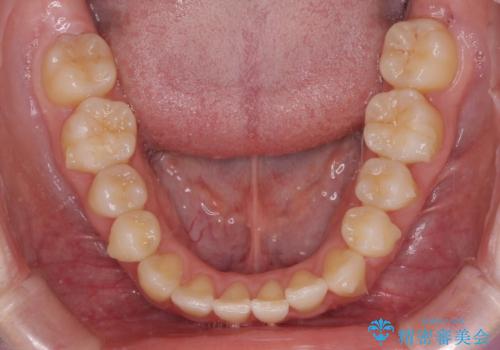

- ちょっとしたデコボコを整えたいとのことで来院された患者様です。

歯列不正は軽微であったため、インビザライン・ライトにより、費用を抑えて矯正治療を行うこととしました。

上下前歯の捻れが改善され、患者様には大変満足していただきました。